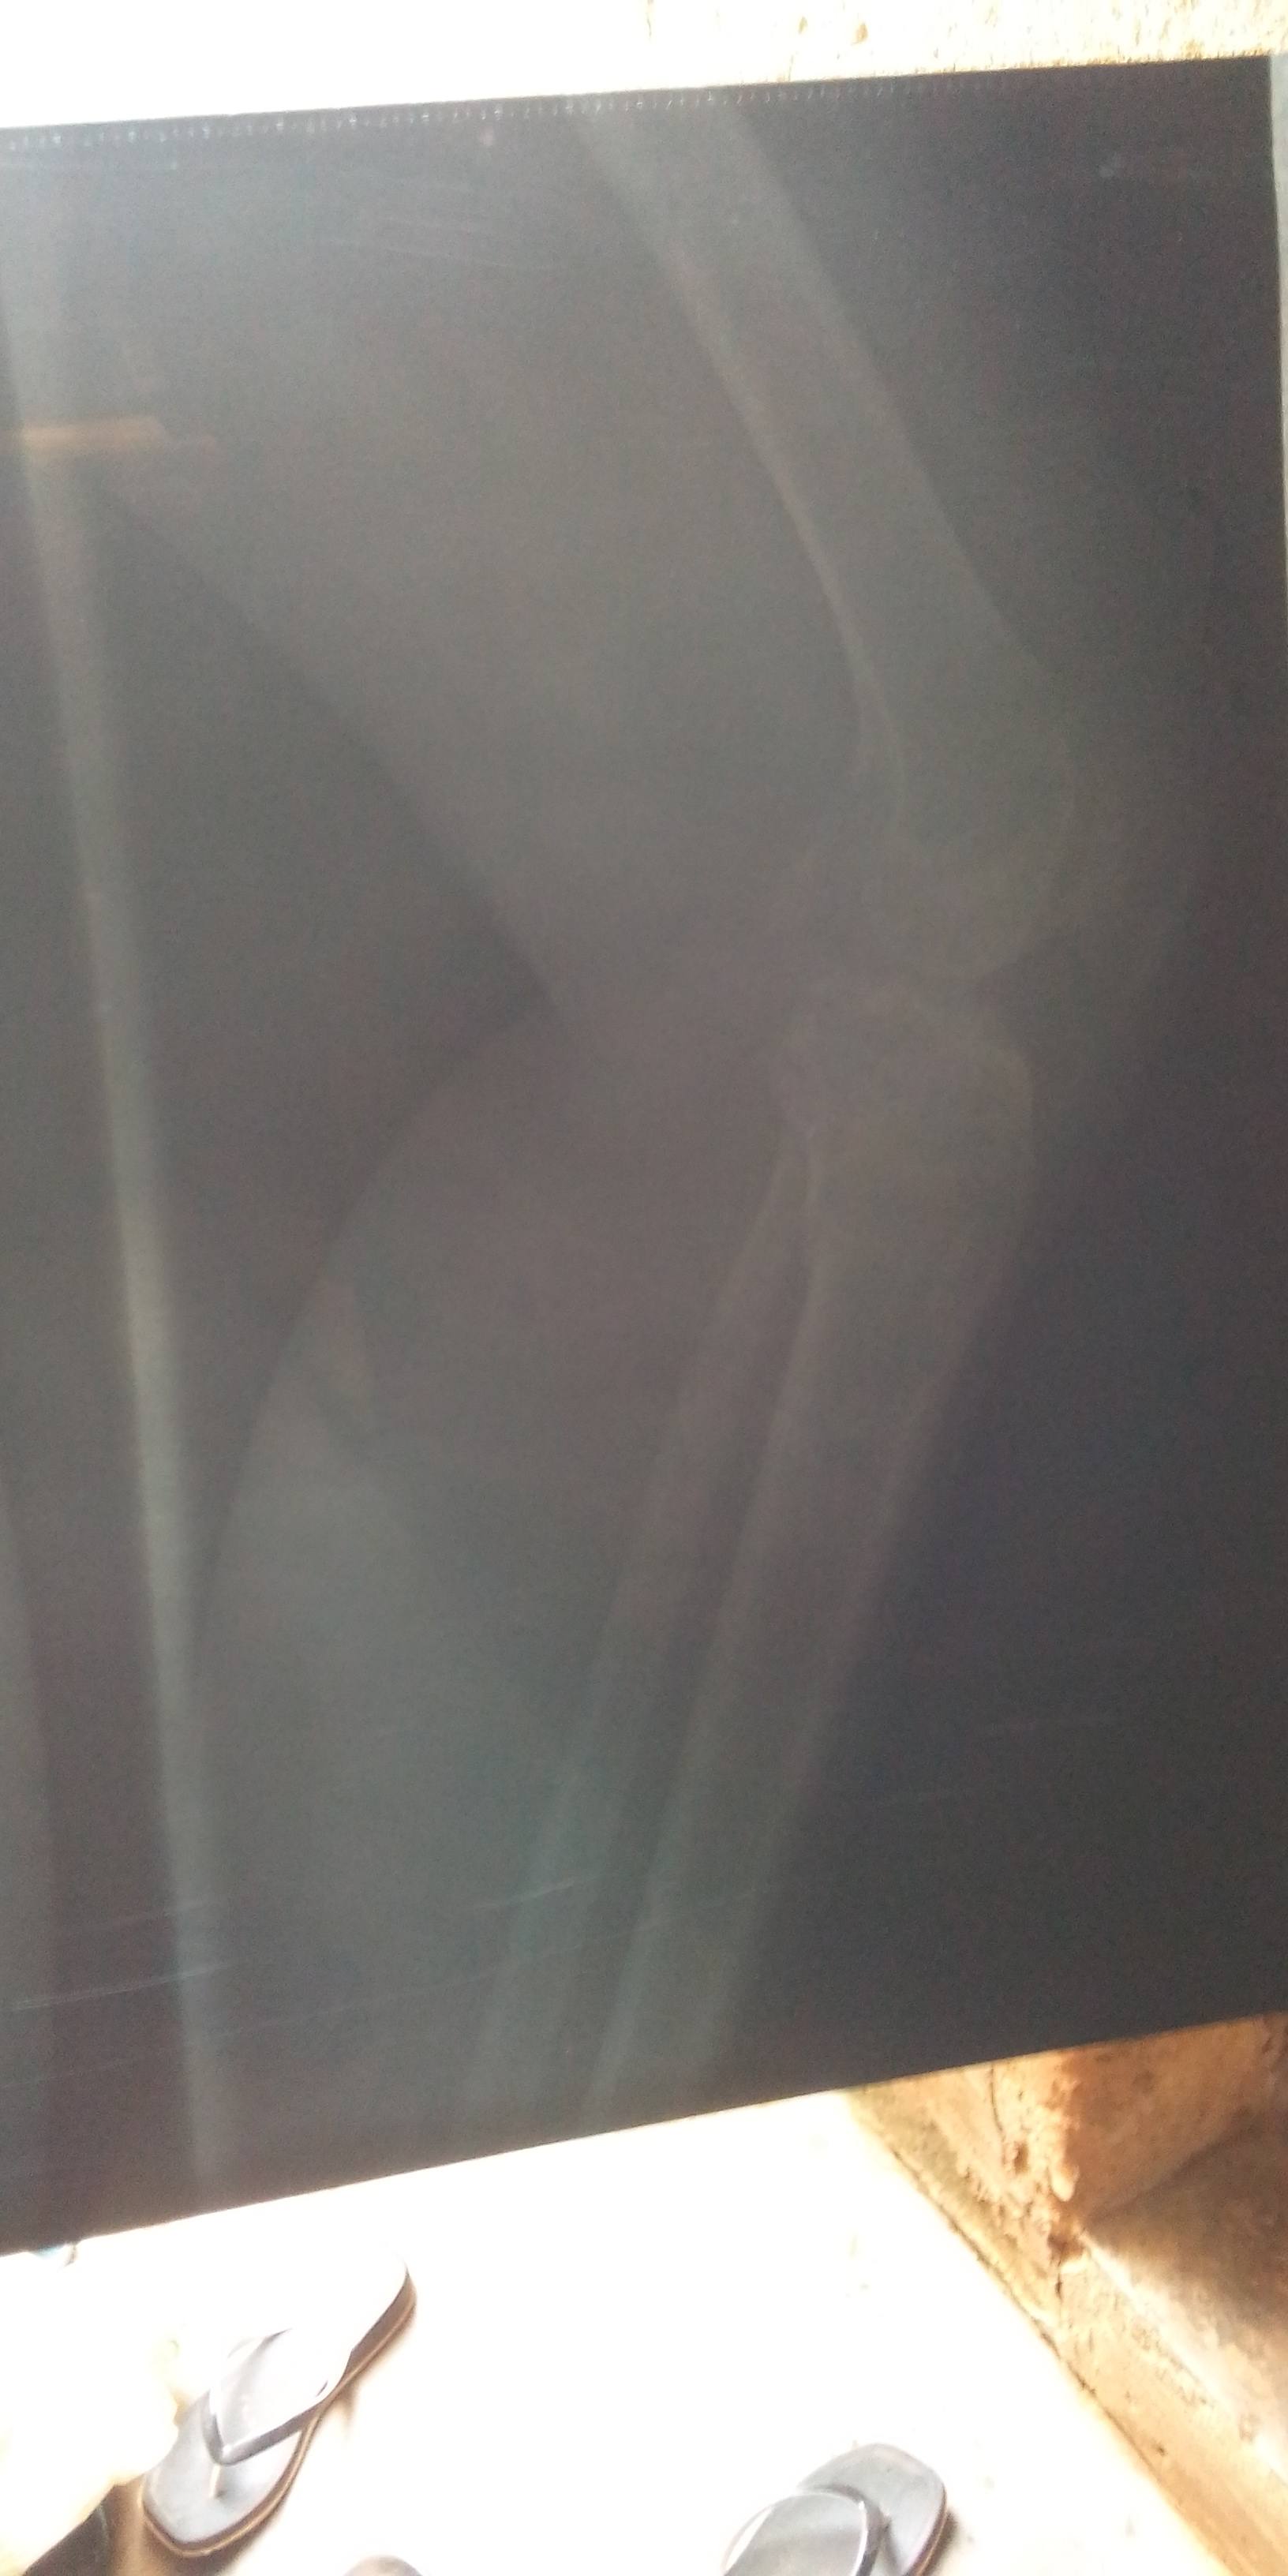

Name: Anifowose Gbemisola

Mobile: 09032539682